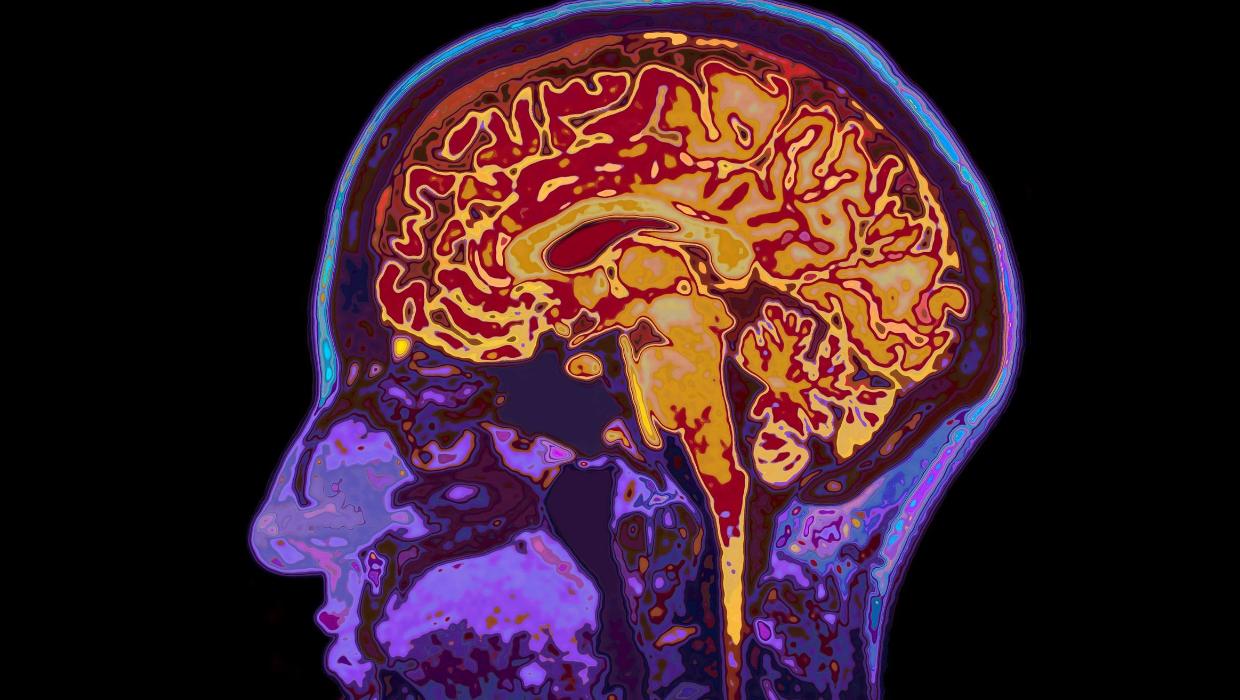

New research from the University of Cambridge reveals that brain development continues until age 32, challenging previous notions about the timeline of cognitive maturity. This study identifies five significant epochs of brain development, highlighting four crucial turning points that shape cognitive functions throughout a person’s life.

The study, titled “A comprehensive analysis of brain development,” illustrates how the brain undergoes profound changes during specific life stages. Researchers conducted an extensive review of existing literature combined with new data to present a clearer picture of brain maturation.

One of the most striking findings is that the brain remains in a state of adolescence until the early thirties. This period is characterized by ongoing changes in decision-making, emotional regulation, and social behavior. The researchers noted that the brain’s prefrontal cortex, which is essential for reasoning and impulse control, continues to evolve during this time.